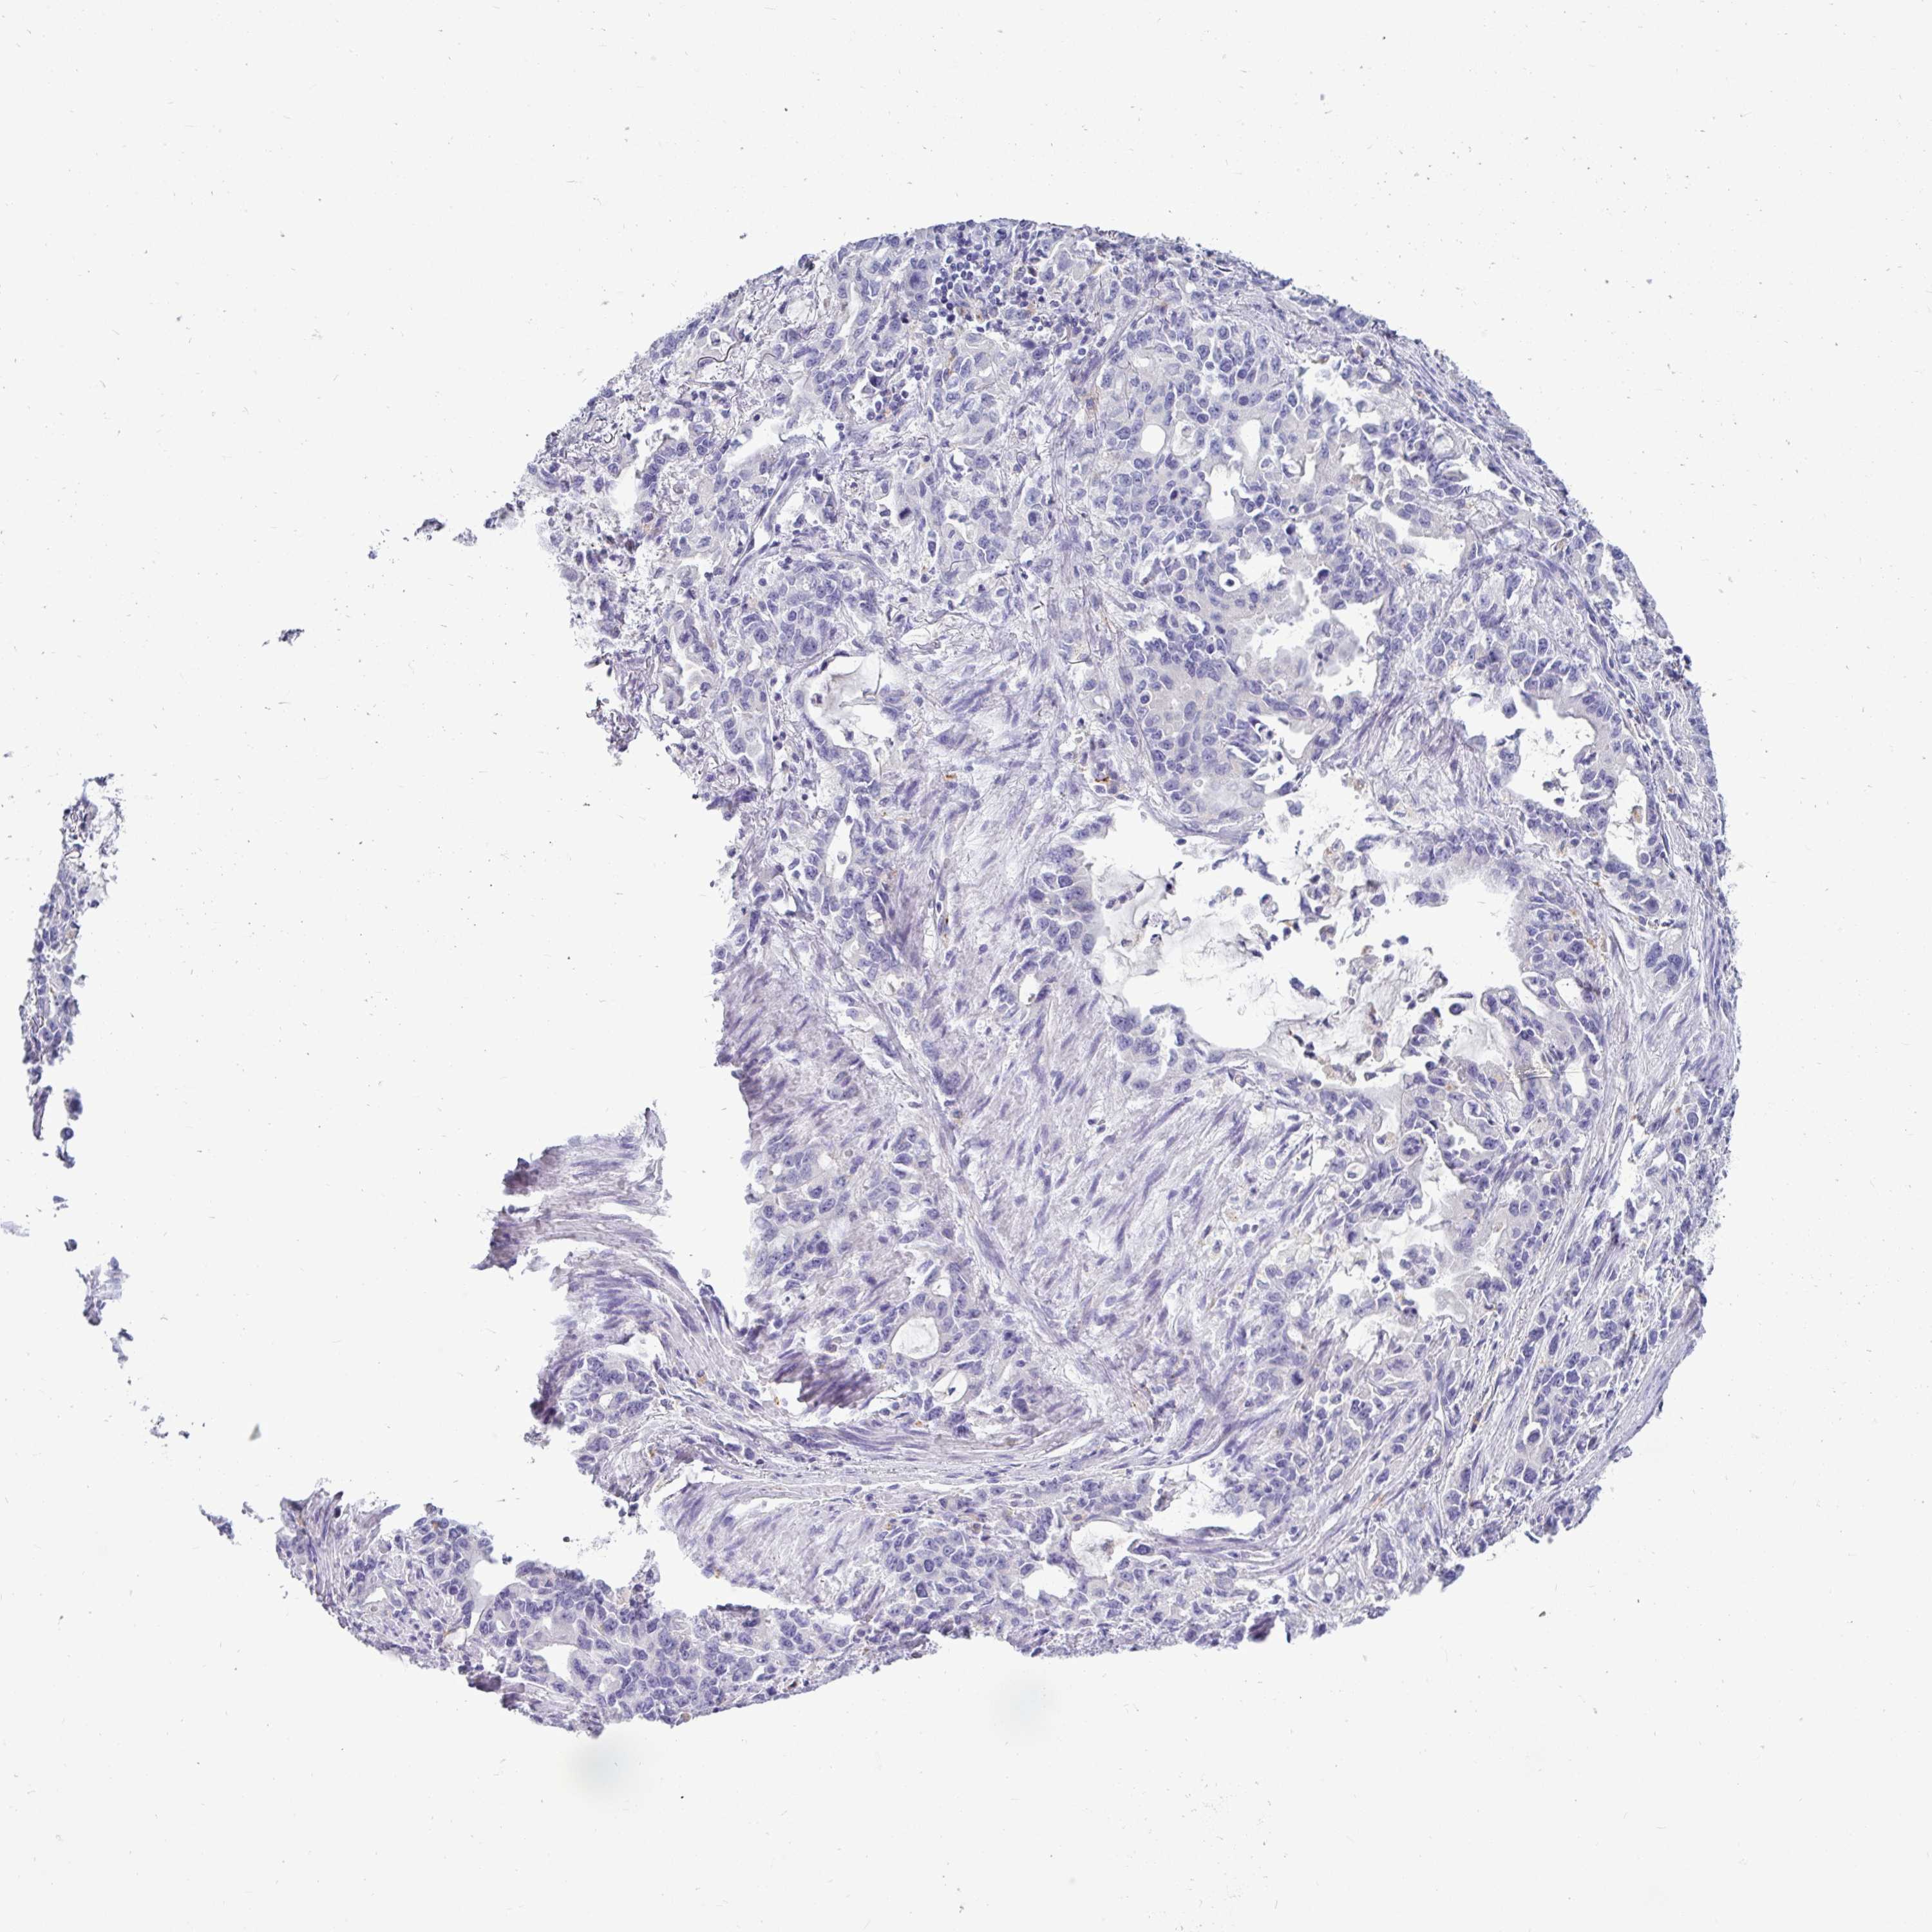

STOMACH CANCER - Protein expressioni

A mouse-over function shows sample information and annotation data. Click on an image to view it in a full screen mode. Samples can be filtered based on level of antibody staining by selecting one or several of the following categories: high, medium, low and not detected. The assay and annotation is described here.

Note that samples used for immunohistochemistry by the Human Protein Atlas do not correspond to samples in the TCGA dataset.

Antibody stainingi

Antibody staining in the annotated cell types in the current human tissue is reported as not detected, low, medium, or high, based on conventional immunohistochemistry profiling in selected tissues. This score is based on the combination of the staining intensity and fraction of stained cells.

Each image is clickable and will lead to virtual microscopy that enables deeper exploration of all samples and also displays staining intensity scores, fraction scores and subcellular localization as well as patient and tissue information for each sample.

Antibody CAB025114

Staining

High

Medium

Low

Not detected

Intensity

Strong

Moderate

Weak

Negative

Quantity

>75%

75%-25%

<25%

None

Location

Nuclear

Cytoplasmic/membranous

Cytoplasmic/membranous,nuclear

Adenocarcinoma, NOS